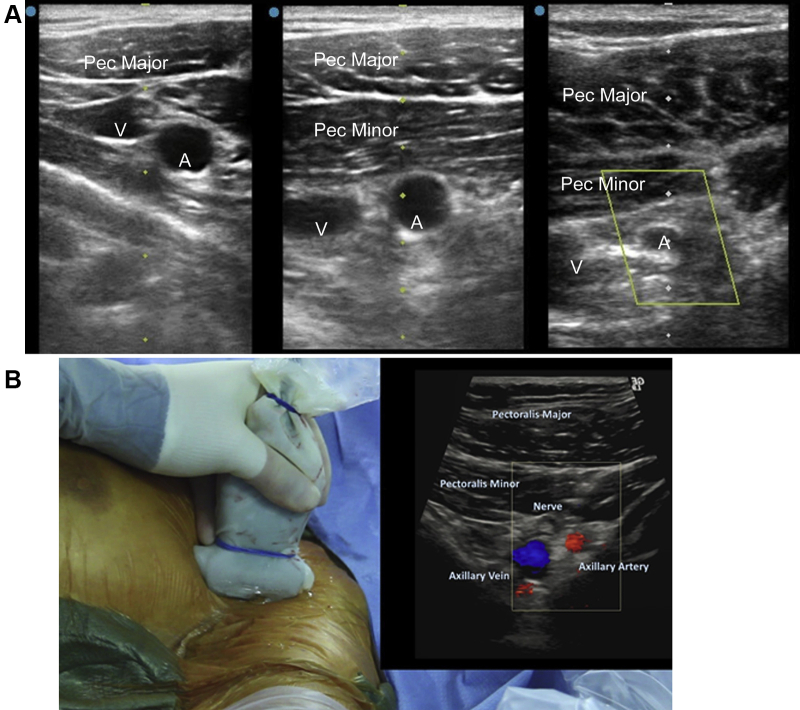

Figure 2.

Upper row: Representative cross-sectional left axillary ultrasound images at the first segment (left), second segment (center) and third segment (right) demonstrating the relationship between the pectoralis muscles (Pec), axillary vein (V), and axillary artery (A). Lower panel: Ultrasound probe with (inset) color Doppler ultrasound image showing a nerve anterior to third axillary artery segment.

Ultrasound imaging allows the operator to identify the pectoralis minor muscle, brachial plexus, and axillary artery and vein, which are distinguished with compression or Doppler flow (Figure 2). Ultrasound provides vessel size information and screening for atherosclerosis without radiation exposure or iodinated contrast. A vascular ultrasound probe (linear array, 5-13 MHz) can be used to image the artery in axial or longitudinal planes, and provide real-time guidance for needle cannulation. A smaller profile probe may be helpful to image between the bony structures. A single anterior wall stick is frequently possible and accuracy is often improved with experience or use of a needle guide.